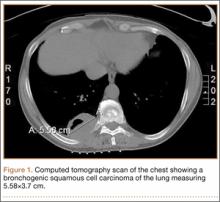

A 56-year-old man presented with right-sided pleuritic flank pain, along with a 30-lb weight loss over a 6-month period. A computed tomographic scan revealed a 5.58×3.7-cm cavitary lesion in the right lower lobe with abutment of the posterior chest wall (Figure 1). He underwent biopsy and staging, and was found to be T3N1, with biopsy-proven well-differentiated bronchogenic squamous cell carcinoma. The patient then underwent right lower and middle lobectomy with concomitant en-bloc resection of the posterior portion of ribs 7 to 11, along with mediastinal lymph-node dissection with negative margins. After surgery, he was treated with 4 cycles of adjuvant chemotherapy with cisplatin and docetaxel.